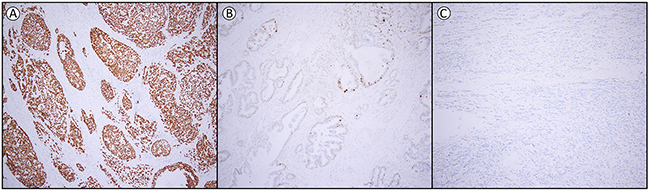

The optimal cut-off for p53 expression was calculated, based on the receiver operating characteristics (ROC) curve and Youden-index (see Supplementary Table 2 and Supplementary Figure 1), into three groups, namely loss of expression (0% of tumor cells positive), heterogeneous expression (1-60% of tumor cells positive) and overexpression (61-100% of tumor cells positive). The interobserver variation for the assessment of p53 between the two observers was excellent (kappa 0.850, p<0.001). From the 204 patients, 55.9% (n=114) of the EAC showed overexpression, 26.5% (n=54) loss of expression, while 17.6% (n=36) had a heterogeneous expression. In all cases this was a homogeneous expression pattern throughout the cancer, of which representative examples are shown in Figure 1.

Figure 1: Examples of p53 expression in esophageal adenocarcinoma. (A) overexpression (61-100% positive tumor cells) (B) heterogeneous expression (1-60% positive tumor cells) and (C) loss of expression (0% positive tumor cells). Magnification 1:100.